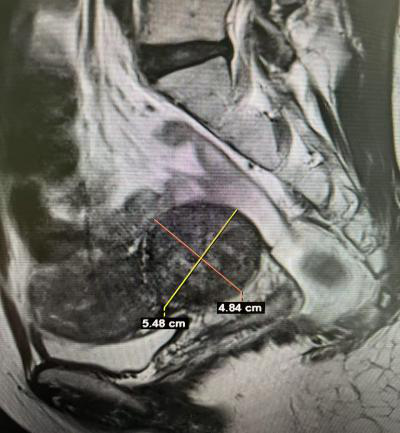

7月8日,37歲的張女士因月經(jīng)量增多收治我院婦科。彩超提示,患者子宮肌瘤(5.7cm×5.3cm×4.8cm),因經(jīng)量增多引起繼發(fā)性貧血,手術(shù)指征明確。